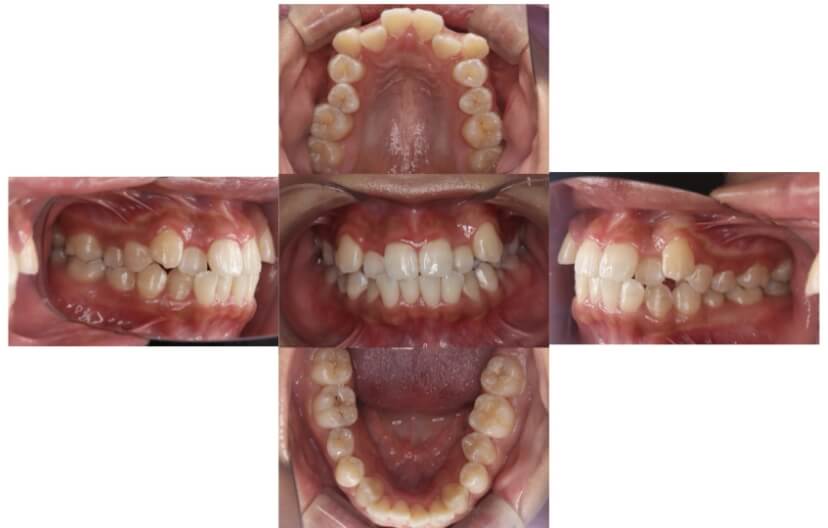

症例1

上顎前突、叢生

抜歯

ブラケット矯正

上下顎叢生、上顎前突(出っ歯、上下の前歯のガタガタ)のケースです。

装置はラビアル(上下表側)で、上顎の小臼歯を2本抜歯を行っています。抜歯したスペースを使って、上の前歯の後方移動と叢生(ガタガタ)と出っ歯の改善を行っています。下は歯と歯の間にIPR(隣接面削合)を行い、スペースを確保し、叢生の改善を行っています。

主訴 前歯のガタガタと出っ歯が気になる。

年齢・性別 47歳 女性

お住まいの地域 神奈川県川崎市

治療方針 抜歯スペースおよびIPRを利用して上前歯の叢生(ガタガタ)の改善

抜歯部位 上顎左右第一小臼歯

使用装置 ラビアル(上下表側)、顎間ゴム

治療期間 2年0か月

治療回数 15回

リテーナー クリアリテーナー

BEFORE

AFTER